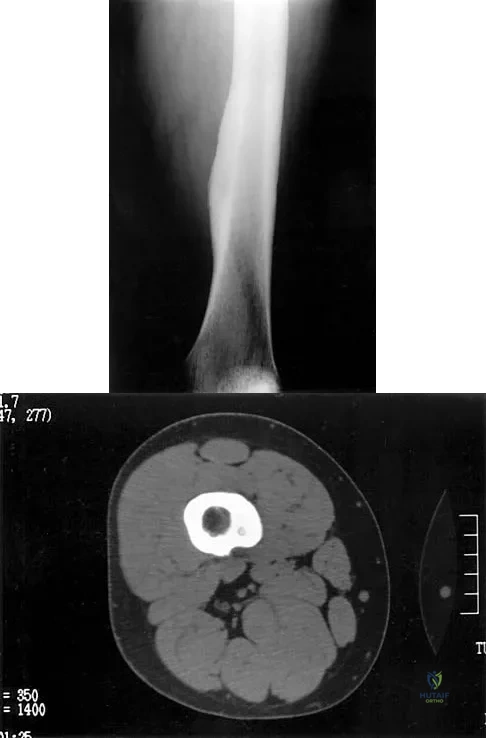

Figures 21a and 21b show the radiograph and CT scan of a 14-year-old patient with thigh pain. The next most appropriate step in management should consist of

An 18-year-old boy reports increasing pain with weight bearing on his right leg and at night. Examination reveals swelling around the right midcalf. Radiographs and an MRI scan are shown in Figures 13a through 13c, and a biopsy specimen is shown in Figure 13d. What is the preferred treatment?

A 66-year-old man has a high-grade angiosarcoma of the right tibia. A radiograph is shown in Figure 43. Treatment should consist of

A 20-year-old patient has foot pain. A radiograph and T1-weighted MRI scan are shown in Figures 8a and 8b. A biopsy specimen is shown in Figure 8c. Treatment should consist of